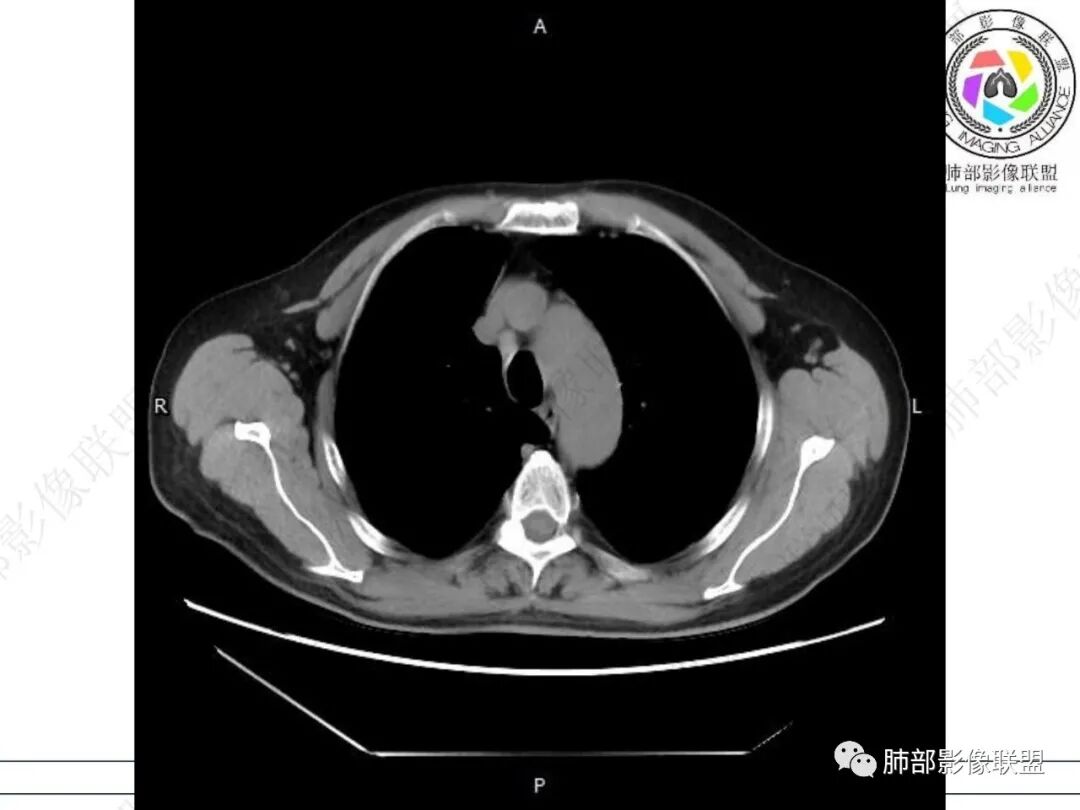

右肺下叶背段可见斑片状、条片状高密度影,支气管扩张,周围伴有磨玻璃影,边界欠清,纵隔窗:可见脊柱偏右侧可见斑片状影,与食管交界面欠清,食管形态不规则,考虑食管支气管瘘?食管异物穿孔?支气管异物?建议食管镜及支气管镜检查。

气管隆突下团片影,其内积气,与食道分界不清,食道壁增厚,管腔狭窄,右下肺实变影,支气管壁增厚,考虑食管支气管瘘并右下肺感染,食道肿瘤病变不除外

支持食管支气管瘘(考虑食管癌)伴后纵隔及右肺感染,食管管壁明显增厚,管腔狭窄,相邻右侧后纵隔内软组织内可见气体影,与食管分界不清,右肺有实变及不张。

右肺下叶背段条片状实变影,内可见支气管走行,支气管有狭窄有扩张,周围可见磨玻璃影,隆突下团片影,内密度不均可见气体影,与周围结构界限不清。食管下段壁增厚,管腔狭窄,右肺下叶慢性炎、肺不张,考虑食道肿瘤所致气管食管瘘。

右肺下叶沿肺叶肺段分布斑片、条片状影,以下叶背段为显,边缘模糊,内可见支气管走行,局部支气管管壁增厚,右侧胸腔少量积液。纵隔隆突下可见不均匀软组织密度影,与周围结构分界不清,内见气体密度影,与食管及相邻右肺支气管之间未显示通道。邻近食管下段壁明显不规则增厚,增强后食管管壁明显不均匀强化,可见线样强化的连续完整粘膜影。